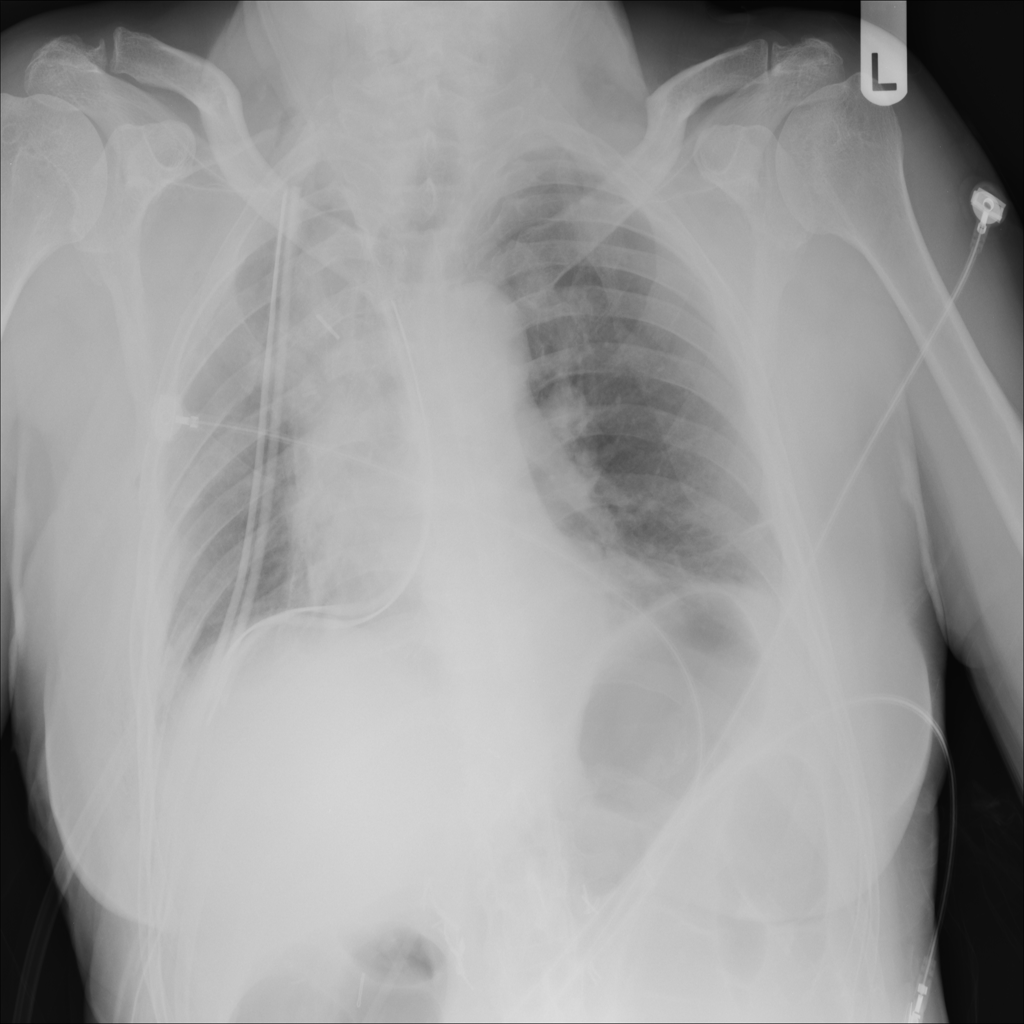

PAT-4639 · IMG-020Pneumothorax

PAT-4639 · IMG-020

PA